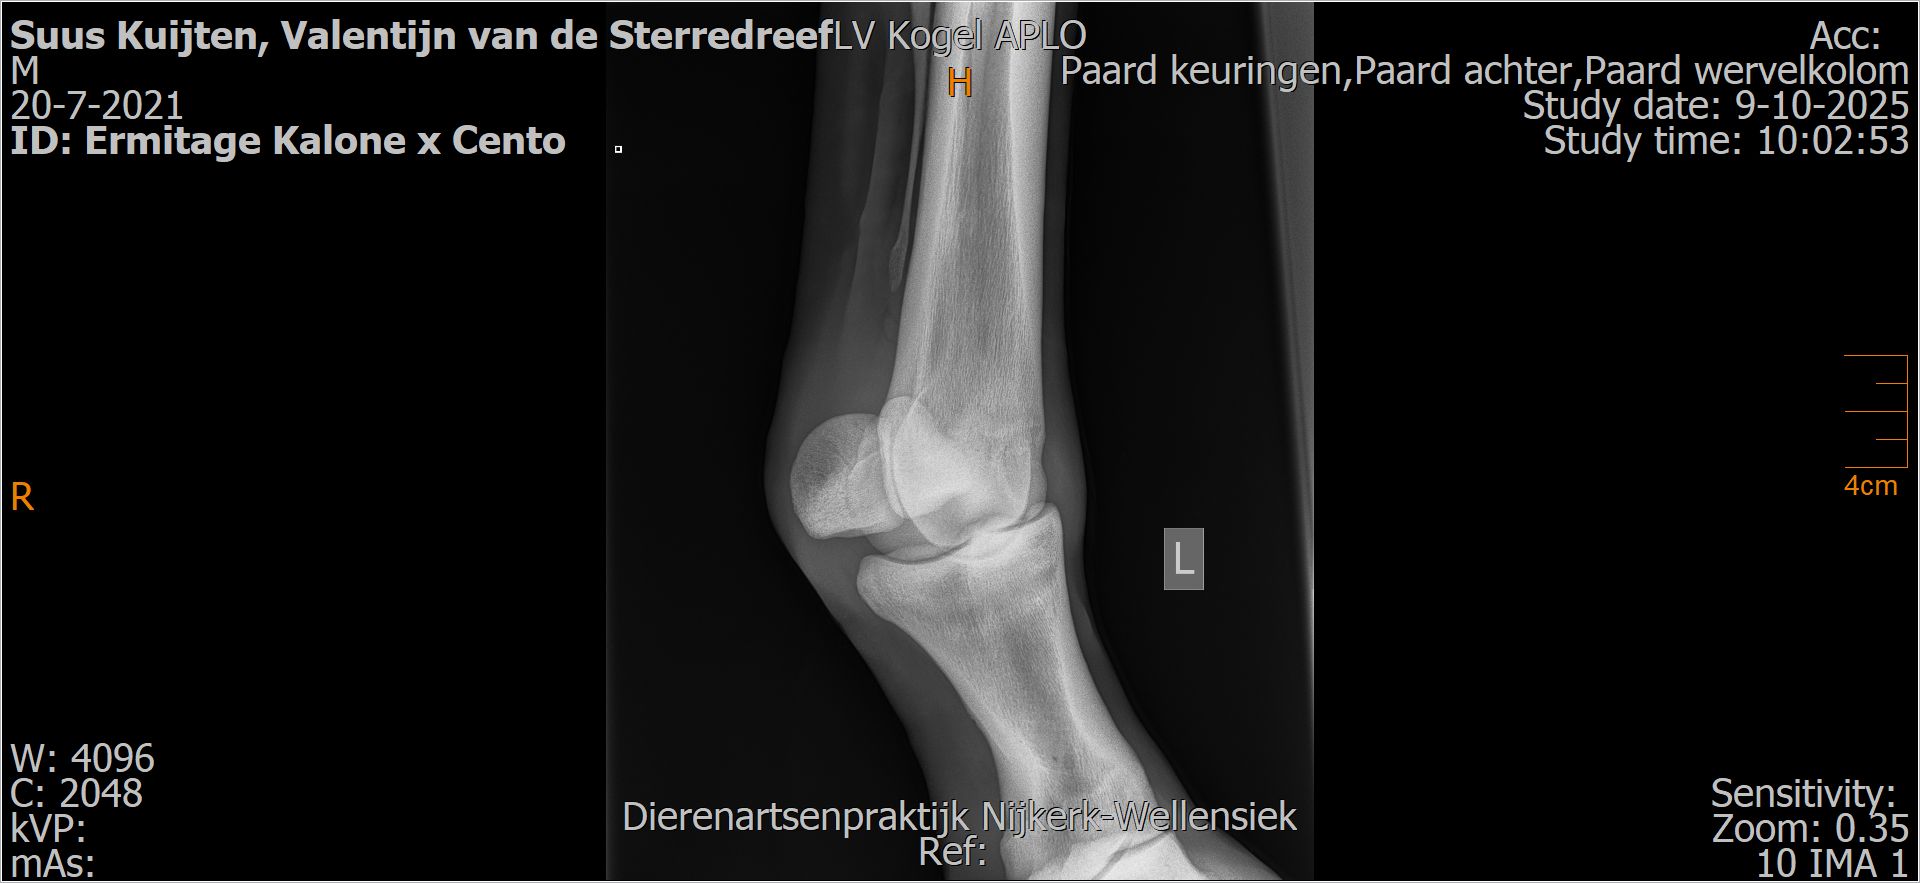

Valentijn van de Sterredreef

Leeftijd:

4

Röntgenfoto’s